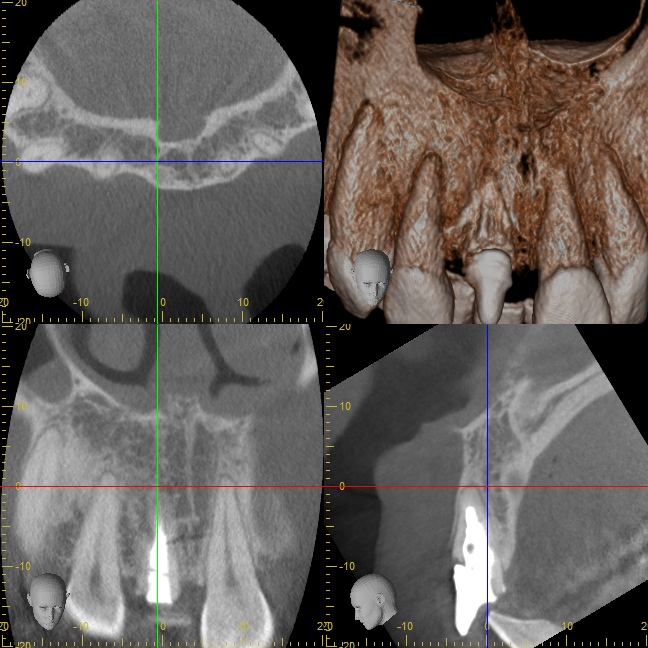

オペ中の口腔内写真とCT写真